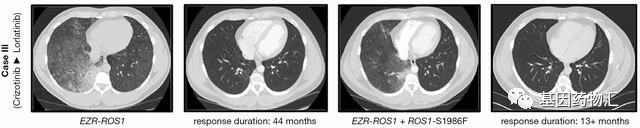

案例二:44+13个月

这位男性患者非常年轻,32岁,只有非常轻微的吸烟史(1包年),诊断为晚期肺腺癌,双肺及腋窝淋巴结都有转移病灶。FISH检查提示存在ROS1重排(67.5%)。

患者一线便接受了克唑替尼治疗,持续缓解整整44个月!后续在右下肺发现了新的病灶,并重新接受了基因检测(二代测序),并确认了耐药突变EZR-ROS1融合以及ROS1-S1986F突变。

患者二线接受了劳拉替尼治疗,至当前随访13个月,疗效仍在持续。